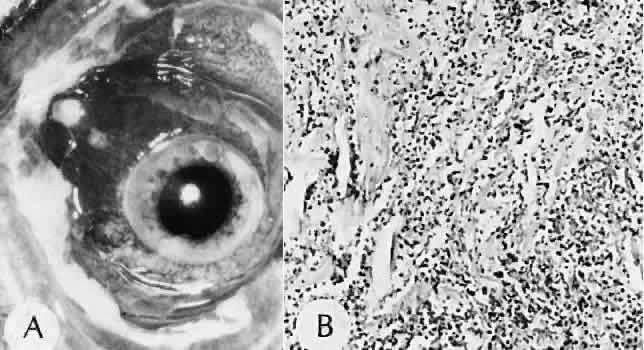

Fig. 31. A case of choroidal detachment. A. By fundus reflex, a large dome-shaped mass can be seen originating from the choroid. The differential diagnosis would include uveal malignant melanoma. In this case, the clinical findings were due to choroidal detachment from the sclera because of fluid accumulating in the suprachoroidal space following cataract surgery. B. The histologic section from another case of choroidal detachment illustrates the location (arrow) and extent of the detachment. In this case the detachment extends to the region of the ciliary body limited anteriorly by the attachment of the choroid to the scleral spur. The displacement of the ciliary body will result in apparent shallowing of the anterior chamber. (Hematoxylin-eosin stain; × 6.)